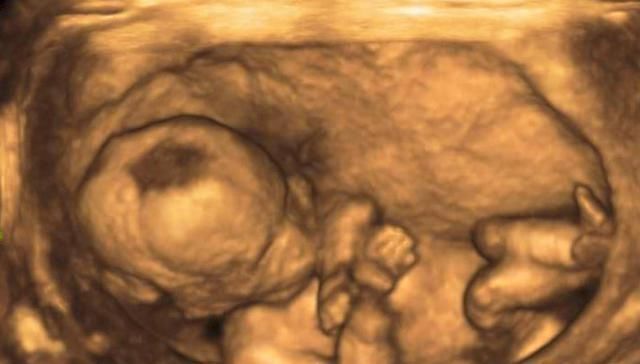

怀孕期间,尤其是宝宝不断长大之后,一般会去医院做四维彩超检查。这个时候从四维彩超检查上可以看到宝宝的相貌,甚至是一些身体的细节。我们都知道去医院做检查的时候,医生不会直接向你透露宝宝的性别,但是孕妈可以细心观察,或许从这几件事上就能够看出宝宝的性别了。

做四维彩超检查的时候是允许家属陪同的,这个时候家属医生也愿意和家属以及孕妇来分享一下宝宝的相貌。所以在聊天的过程中,孕妈不妨多多观察一下四维彩超,因为医生一不小心可能就会照到宝宝的隐私部位,这个时候孕妈或许就能够知道宝宝的性别了。